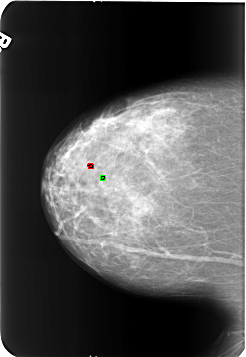

B_3213_1.RIGHT_CC

FILE: B_3213_1.RIGHT_CC.OVERLAY

TOTAL_ABNORMALITIES 2

ABNORMALITY 1

LESION_TYPE CALCIFICATION TYPE ROUND_AND_REGULAR-LUCENT_CENTER DISTRIBUTION N/A

ASSESSMENT 2

SUBTLETY 5

PATHOLOGY BENIGN_WITHOUT_CALLBACK

TOTAL_OUTLINES 1

BOUNDARY

ABNORMALITY 2